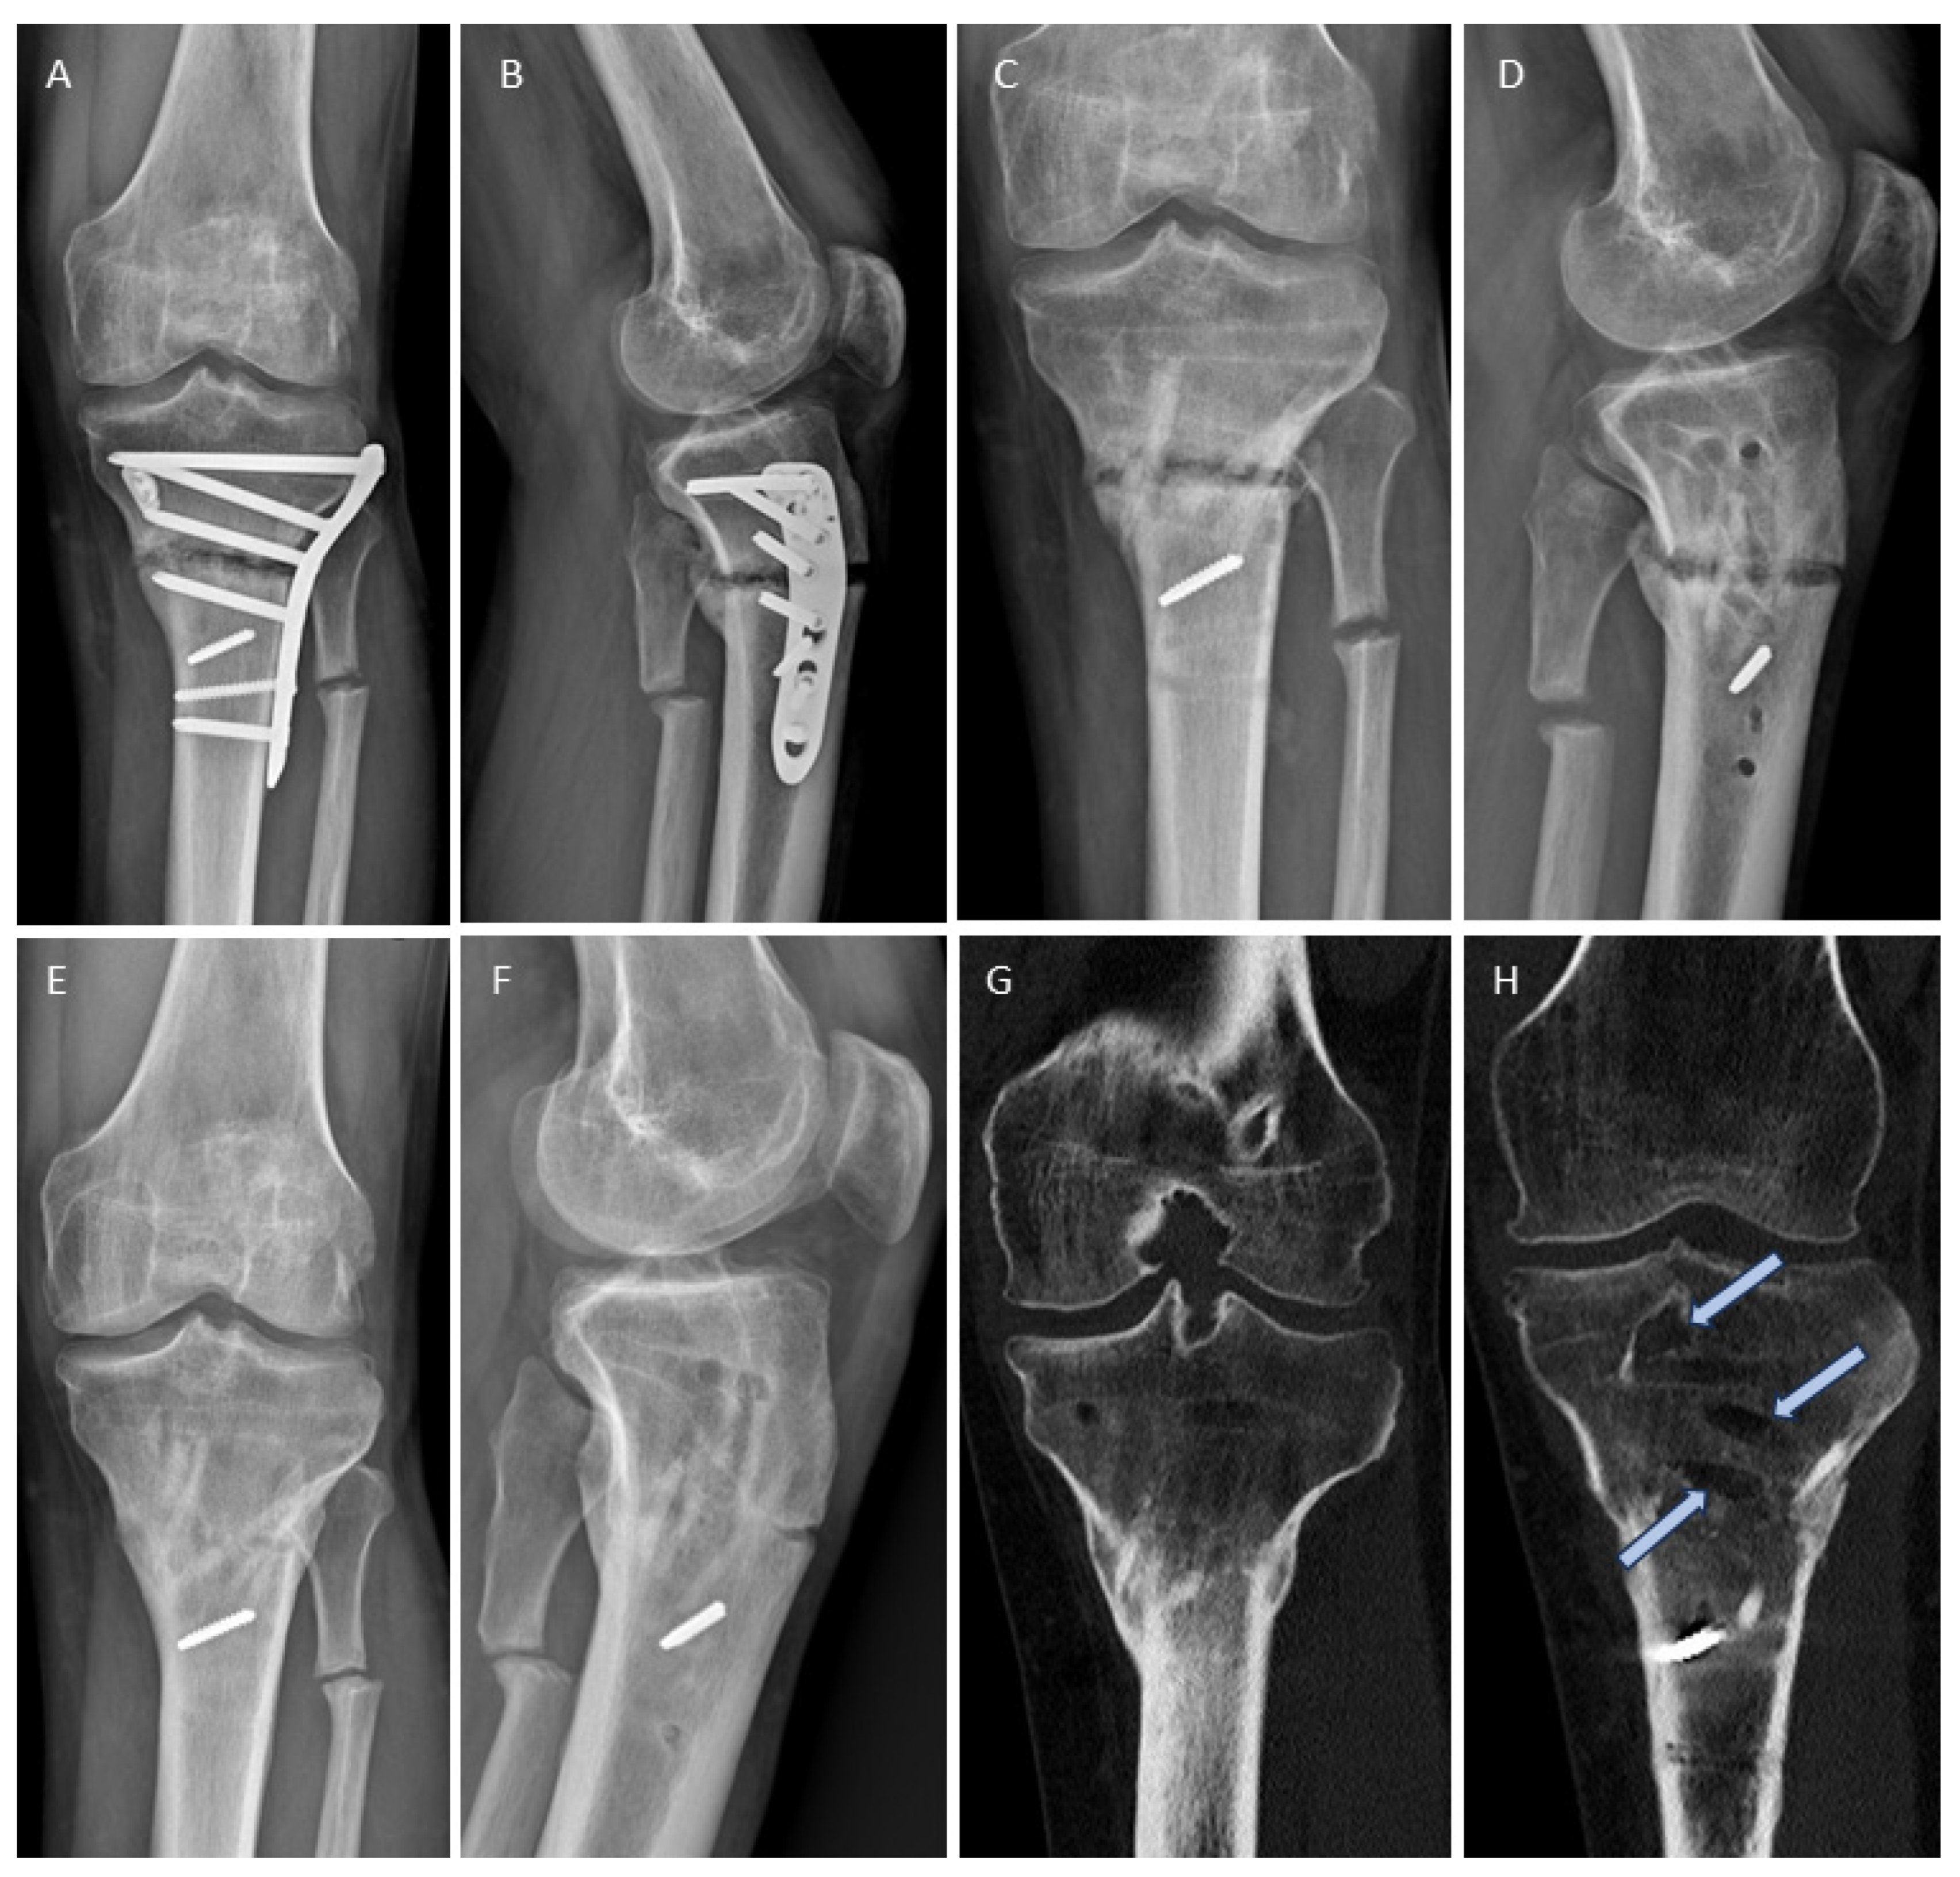

3.4. Examples for Bone Healing

3.6. Radiological Findings of Interest